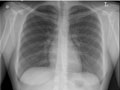

Los pulmones tienen un aspecto normal en cuanto al tamaño y a la forma, y el tejido de los pulmones tiene un aspecto normal. No pueden observarse crecimientos ni otras masas dentro de los pulmones. Los espacios pleurales (los espacios que rodean los pulmones) también tienen un aspecto normal. Vea una radiografía de pecho normal. |

El corazón tiene un aspecto normal en cuanto al tamaño y a la forma, y el tejido cardíaco tiene un aspecto normal. Los vasos sanguíneos que van al corazón y que salen de este también son normales en cuanto al tamaño, a la forma y a la apariencia. |

Los huesos, incluidas la columna vertebral y las costillas, tienen un aspecto normal. |

El diafragma tiene un aspecto normal en cuanto a la forma y a la ubicación. |

No se observa una acumulación anormal de líquido o aire; tampoco se observan objetos extraños. |

Todas las sondas, los catéteres u otros dispositivos médicos están en su posición correcta en el pecho. |